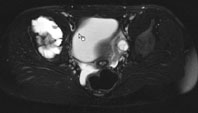

Die Röntgenuntersuchung von Becken/Hüfte zeigt eine septierte geographische Osteolyse in der Ala und im Korpus des Os Iliums rechts. Das Röntgenbild und die Aufnahmen der nachfolgenden MRI-Untersuchung sehen Sie hier:

T1 FS, axial, 5 mm

Bild vergrössern